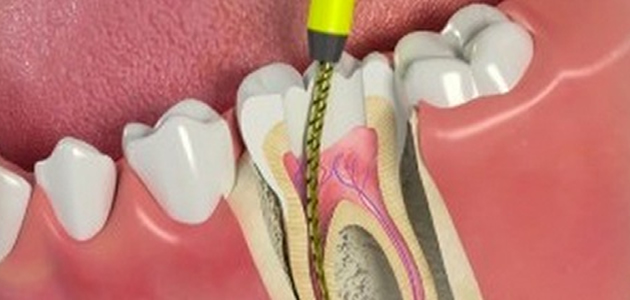

Inside the tooth, under the white enamel and a hard layer called the dentin, is a soft tissue called the pulp. The pulp contains blood vessels, nerves and connective tissue, and helps to grow the root of your tooth during development. In a fully developed tooth, the tooth can survive without the pulp because the tooth continues to be nourished by the tissues surrounding it.

The first step in placing a post is performing root canal therapy on the tooth to remove the infection and shape the root canal to receive the post. We’ll use a small instrument called a dental file to shape the top of the root canal, select a post, and then cement or bond it in place. After the post is in place, we fill the tooth with the new core material. Once it has hardened, the core material is shaped and prepared to receive a crown. We then take an impression of your teeth so a dental laboratory can custom-craft a crown that will precisely fit your tooth.